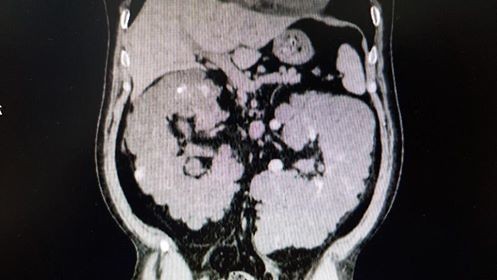

استئصال كليه متكيسه كبيره

استئصال كليه متكيسه كبيره في المستشفي السعودي الألماني بالرياض

تمكن الفريق الطبي بقسم المسالك البولية بالمستشفى السعودي الألماني بالرياض من استئصال الكليه اليسري متعدده الأكياس بحجم يتجاوز ٣٠ سنتيمتر.

و كان المريض صاحب ال٤٨ عام يعاني من الآلام شديده في البطن مع ارتفاع بدرجه الحراره.

و باجرا الفحوصات تبين وجود أكياس متعدده ممتلئة بالصديد و التجمعات الدموية، و تم استئصال الكليه اليسري بنجاح علما بأن المريض كان يقوم باجراء الغسيل الكلوي المستمر.

وتم خروج المريض بصحه و عافيه بعد إجراء الجراحة